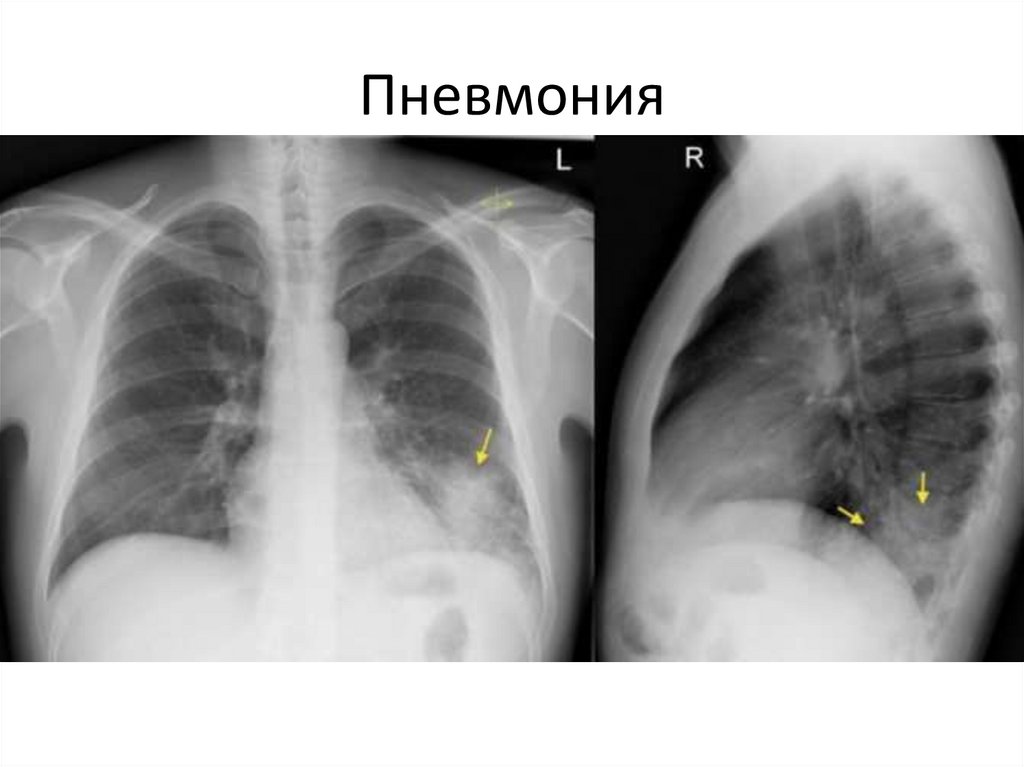

Пневмония

20.